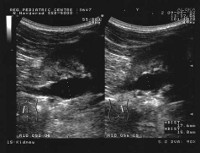

Диабетическая нефропатия является поздним осложнением сахарного диабета 1 и 2 типов и одной из основных причин смерти больных с данным заболеванием. Развивающиеся при диабете повреждения крупных и мелких кровеносных сосудов (диабетические макроангиопатии и микроангиопатии) способствуют поражению всех органов и систем, в первую очередь, почек, глаз, нервной системы.

Диабетическая нефропатия наблюдается у 10-20% больных сахарным диабетом; несколько чаще нефропатия осложняет течение инсулинозависимого типа заболевания. Диабетическую нефропатию выявляют чаще у пациентов мужского пола и у лиц с сахарным диабетом 1 типа, развившемся в пубертатном возрасте. Пик развития диабетической нефропатии (стадия ХПН) наблюдается при продолжительности диабета 15-20 лет.